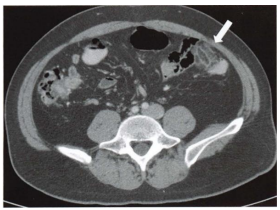

Mulher de 29 anos inicia com dor

abdominal aguda em flanco esquerdo.

O sintoma é bem localizado e a

paciente consegue apontar o local

exato da dor. Realizada tomografia

com contraste endovenoso que

evidencia densificação focal da

gordura pericolônica esquerda, na

borda antimesentérica, com aspecto

em “dedo de luva”, apontado pela

seta na figura abaixo. Assinale a

alternativa com o diagnóstico

CORRETO: